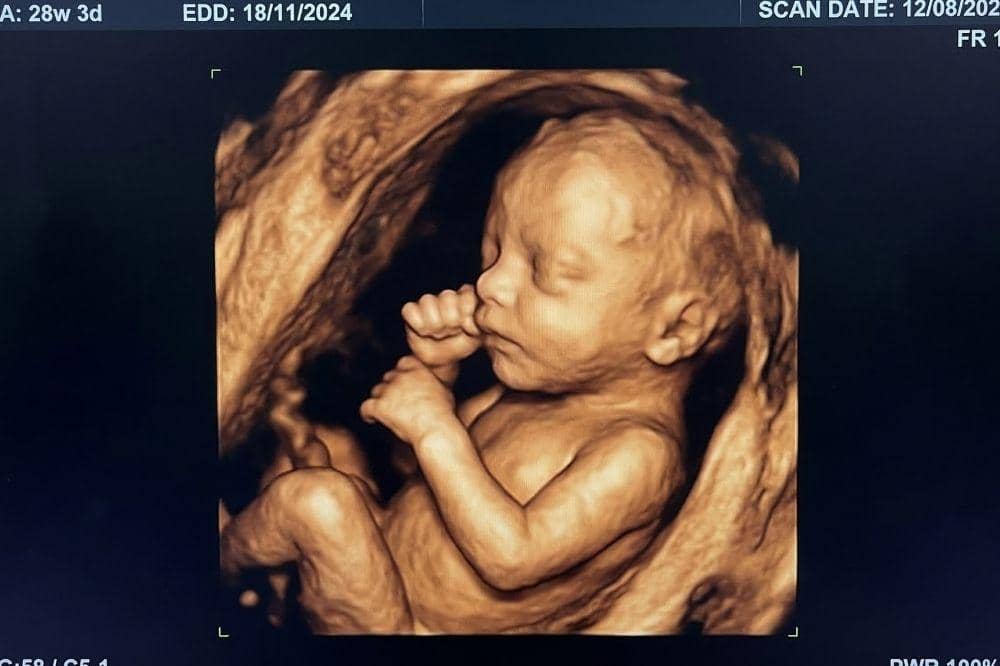

Waktu terbaik melakukan USG 4D adalah pada usia kehamilan 24–30 minggu agar fitur wajah bayi terlihat jelas dan hasil pemeriksaan optimal.

Untuk menentukan waktu terbaik dalam melakukan USG 4D, Mama sebaiknya mempertimbangkan untuk melakukan pemeriksaan USG 4D pada usia kehamilan trimester kedua hingga awal trimester ketiga, yaitu pada usia kehamilan 24–30 minggu.

Dokter Spesialis Obstetri dan Ginekologi dr. Marcel lewat Instagramnya, @marcel.elian.suwito, mengatakan bahwa usia kehamilan tersebut merupakan waktu yang tepat dalam melakukan pemeriksaan USG 4D karena bayi telah memiliki lapisan lemak yang cukup sehingga bentuk wajah serta beberapa bagian tubuh lainnya mulai terbentuk dan terlihat jelas pada hasil USG 4D.

Apabila Mama melakukan pemeriksaan terlalu dini, kondisi bayi masih tidak dapat terlihat dengan jelas karena lapisan lemak subkutan belum terbentuk dengan baik.

Sebaliknya, jika Mama melakukan pemeriksaan terlalu lama, posisi bayi akan semakin membesar dan berada lebih rendah di dalam rahim sehingga sulit bagi dokter untuk menangkap gambar wajah bayi dengan baik.

Pemeriksaan USG 4D memberikan kondisi bayi di dalam rahim secara real-time. Mama dapat menyaksikan berbagai aktivitas si Kecil di dalam rahim, seperti meregangkan tubuh, menggerakan tangan, hingga menampilkan ekspresi wajah.

Istilah 4D pada USG ini merujuk pada dimensi keempat sehingga Mama dapat melihat panjang, lebar, dan kedalaman tubuh bayi yang nampak secara nyata dalam visualisasi USG 4D.

Selain menyaksikan kondisi tubuh bayi secara keseluruhan, Mama juga dapat melihat pergerakannya, seperti saat ia meregangkan tubuh, mengisap jempol, menguap, hingga saat ia mengubah ekspresi wajahnya.